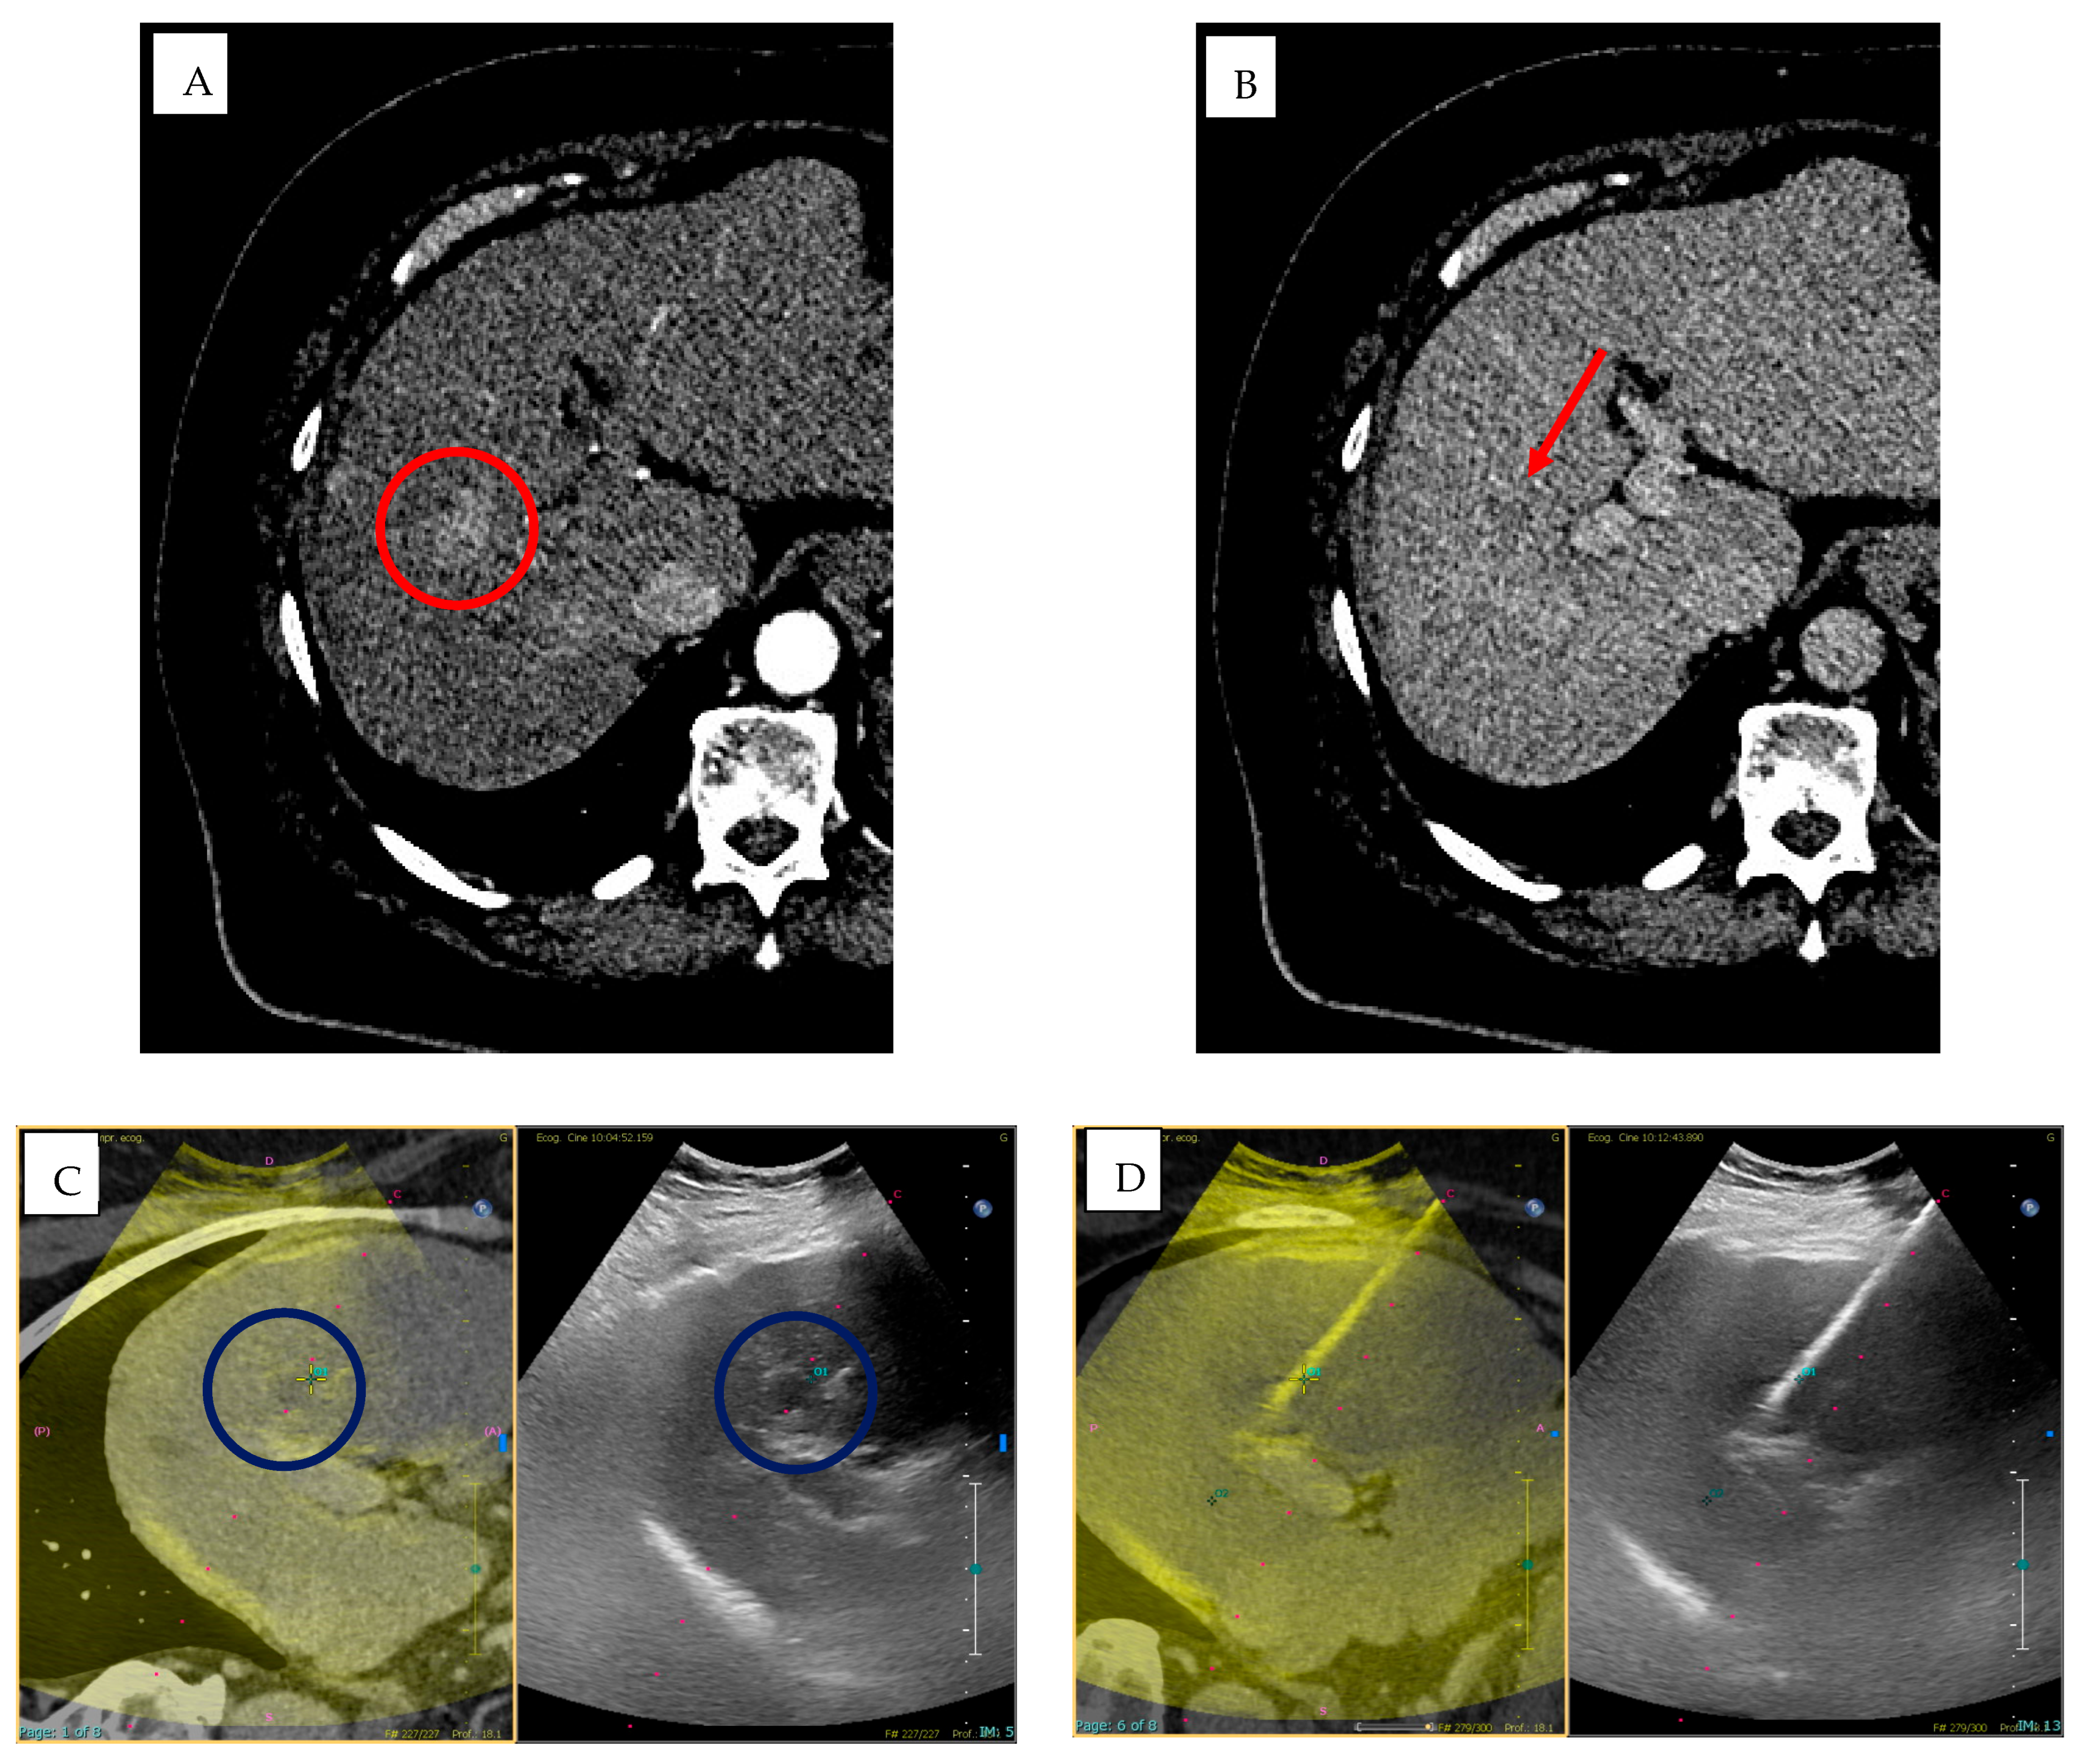

- Biondetti, P.; Ierardi, A.M.; Casiraghi, E.; Caruso, A.; Grillo, P.; Carriero, S.; Lanza, C.; Angileri, S.A.; Sangiovanni, A.; Iavarone, M.; et al. Clinical Impact of a Protocol Involving Cone-Beam CT (CBCT), Fusion Imaging and Ablation Volume Prediction in Percutaneous Image-Guided Microwave Ablation in Patients with Hepatocellular Carcinoma Unsuitable for Standard Ultrasound (US) Guidance. J. Clin. Med. 2023, 12, 7598. [Google Scholar] [CrossRef]